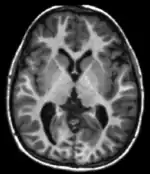

Each tissue returns to its equilibrium state after excitation by the independent relaxation processes of T1 (spin-lattice; that is, magnetization in the same direction as the static magnetic field) and T2 (spin-spin; transverse to the static magnetic field). To create a T1-weighted image, magnetization is allowed to recover before measuring the MR signal by changing the repetition time (TR). This image weighting is useful for assessing the cerebral cortex, identifying fatty tissue, characterizing focal liver lesions, and in general, obtaining morphological information, as well as for post-contrast imaging. To create a T2-weighted image, magnetization is allowed to decay before measuring the MR signal by changing the echo time (TE). This image weighting is useful for detecting edema and inflammation, revealing white matter lesions, and assessing zonal anatomy in the prostate and uterus.

T1 and T2 values are dependent on the chemical environment of the sample; hence their utility in MRI. Soft tissue and muscle tissue relax at different rates, yielding the image contrast in a typical scan.

The standard display of MR images is to represent fluid characteristics in black-and-white images, where different tissues turn out as follows: